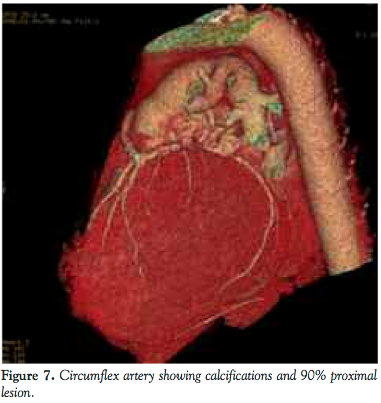

He was admitted for elective cardiac catheterization. Cineangiographic evaluation revealed a single vessel coronary artery arising from the right coronary cusp supplying the entire left system and also the right coronary artery. The right coronary artery was abnormal with significant tortuosity in the proximal and mid segments more consistent with varicose anatomy. Distally the RCA was normal. It gave rise to a posterior descending artery, which had an ostial 60% stenosis. The posterior lateral branch was a small caliber vessel and was normal. The left anterior descending artery (LAD) was a moderate caliber vessel and had no obstructive disease. The first diagonal branch divided into bifurcating branches of which the lower branch had a 70% stenosis. The circumflex artery was a very large caliber vessel that had a proximal 90%-95% stenosis. Left to right collaterals were noted.

CT angiography showed that coronary artery calcium score was 966. All vessels originated in the common origin at the right coronary cusp. The left main was long and normal as it coursed anteriorly to the pulmonary artery before bifurcating. The LAD had diffuse scattered calcifications in the proximal portion, but no critical lesions. The circumflex had diffuse severe calcifications proximally. There was a proximal 90% stenosis, which was mixed plaque. The RCA was dominant. The midportion of the vessel had a corkscrew configuration. Proximal to this was 50% stenosis of soft plaque.